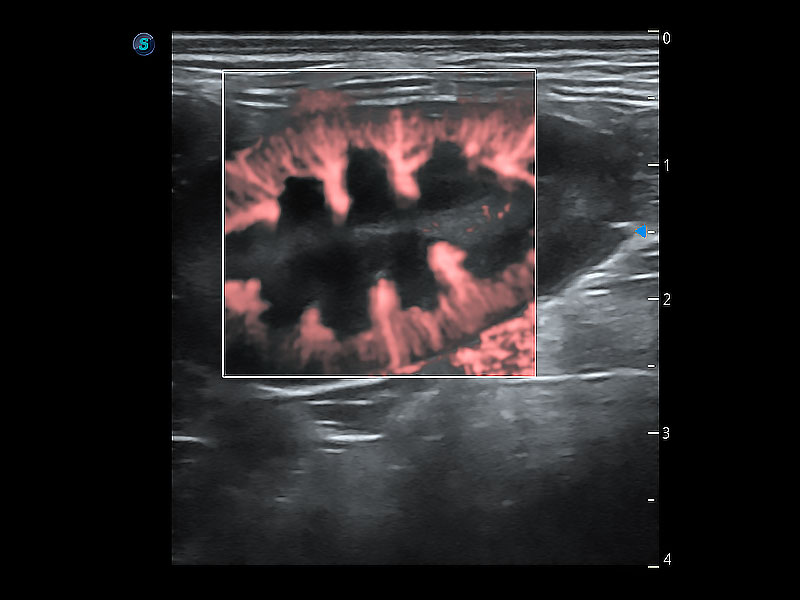

在传统二维血流成像的基础上,呈现血流的立体感,具有动感的生命力之美。即便是微小的血管也能轻松应对,提高了血流的视觉敏感性。

极大提升超低速微细血流的检出能力,同时更精准地滤除软组织和超声信号,为兽用医生提供以往无法通过常规血流获得的疾病诊断信息。